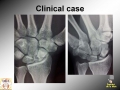

Scaphoid Nonunion

Arthroscopic treatment